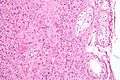

Low magnification micrograph of a Leydig cell tumour. H&E stain. | |

Intermediate magnification micrograph of a Leydig cell tumour. H&E stain.